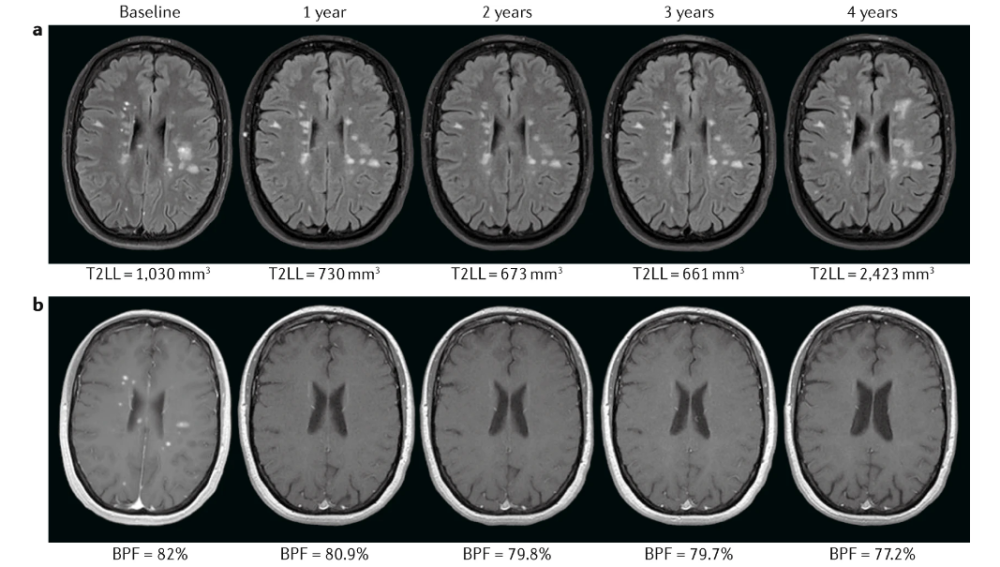

MAGNIMS共识建议:脑和脊髓萎缩在MS临床实践中的应用_腾讯新闻

new.qq.comFrontiers | Functional Connectivity Alterations Reveal Complex

new.qq.comFrontiers | Functional Connectivity Alterations Reveal Complex

www.frontiersin.orgalterations frontiersin mechanisms mild reveal functional clinical remitting radiological connectivity sclerosis relapsing complex multiple status based figure fneur

www.frontiersin.orgalterations frontiersin mechanisms mild reveal functional clinical remitting radiological connectivity sclerosis relapsing complex multiple status based figure fneur

nguyeindo.comBetween-group Differences In Baseline Radiological (a -d), Neurological

nguyeindo.comBetween-group Differences In Baseline Radiological (a -d), Neurological

www.ign.comComplementary Roles Of Grey Matter MTR And T2 Lesions In Predicting

www.ign.comComplementary Roles Of Grey Matter MTR And T2 Lesions In Predicting